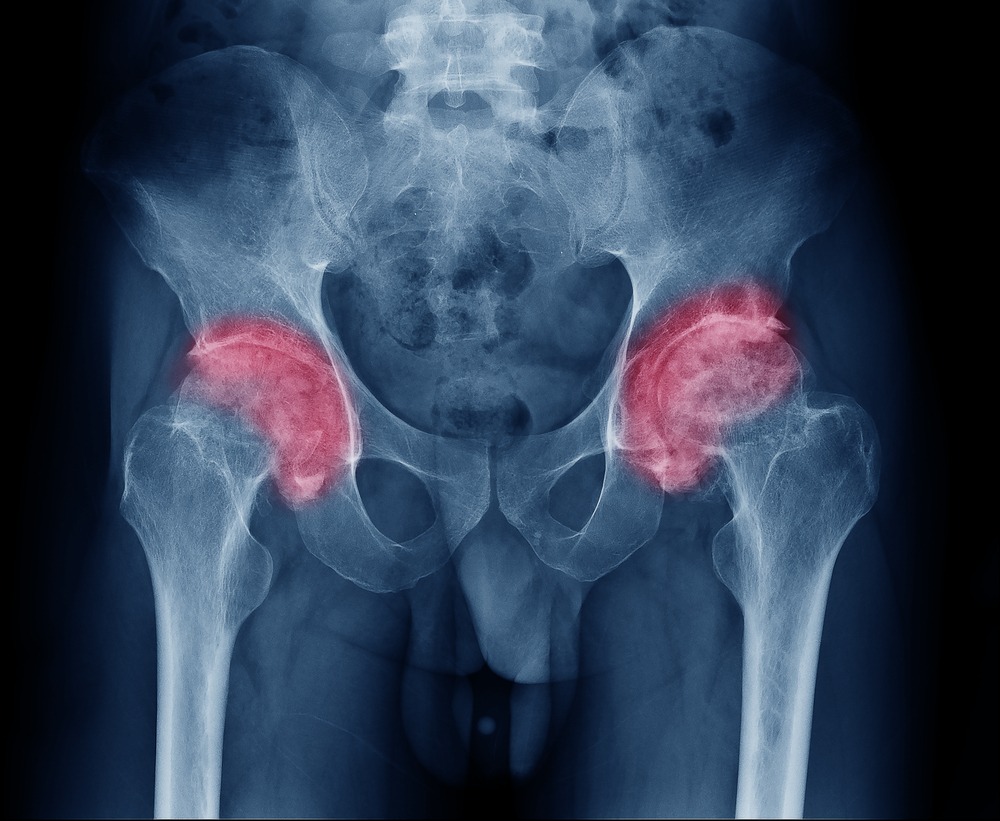

O que é Artrose de Quadril?

É um processo degenerativo da articulação coxo femoral e que normalmente cursa com a presença de dor, redução da amplitude de movimento articular chegando à rigidez, limitando as atividades do dia-a-dia.

Existem duas formas de artrose no quadril, a primária e a secundária. No caso da primária ou idiopática, surge geralmente em pacientes idosos, mais comuns em mulheres, porém afetam ambos os sexos de todos os grupos étnicos. As secundárias afetam tanto jovens quanto idosos, e tem como desencadeante uma situação anterior: Displasia do quadril na infância, Doença de Perthes, Epifisiólise, Sequelas de fraturas de acetábulo ou porção proximal do fêmur, Doenças reumáticas e Necrose da cabeça femoral.